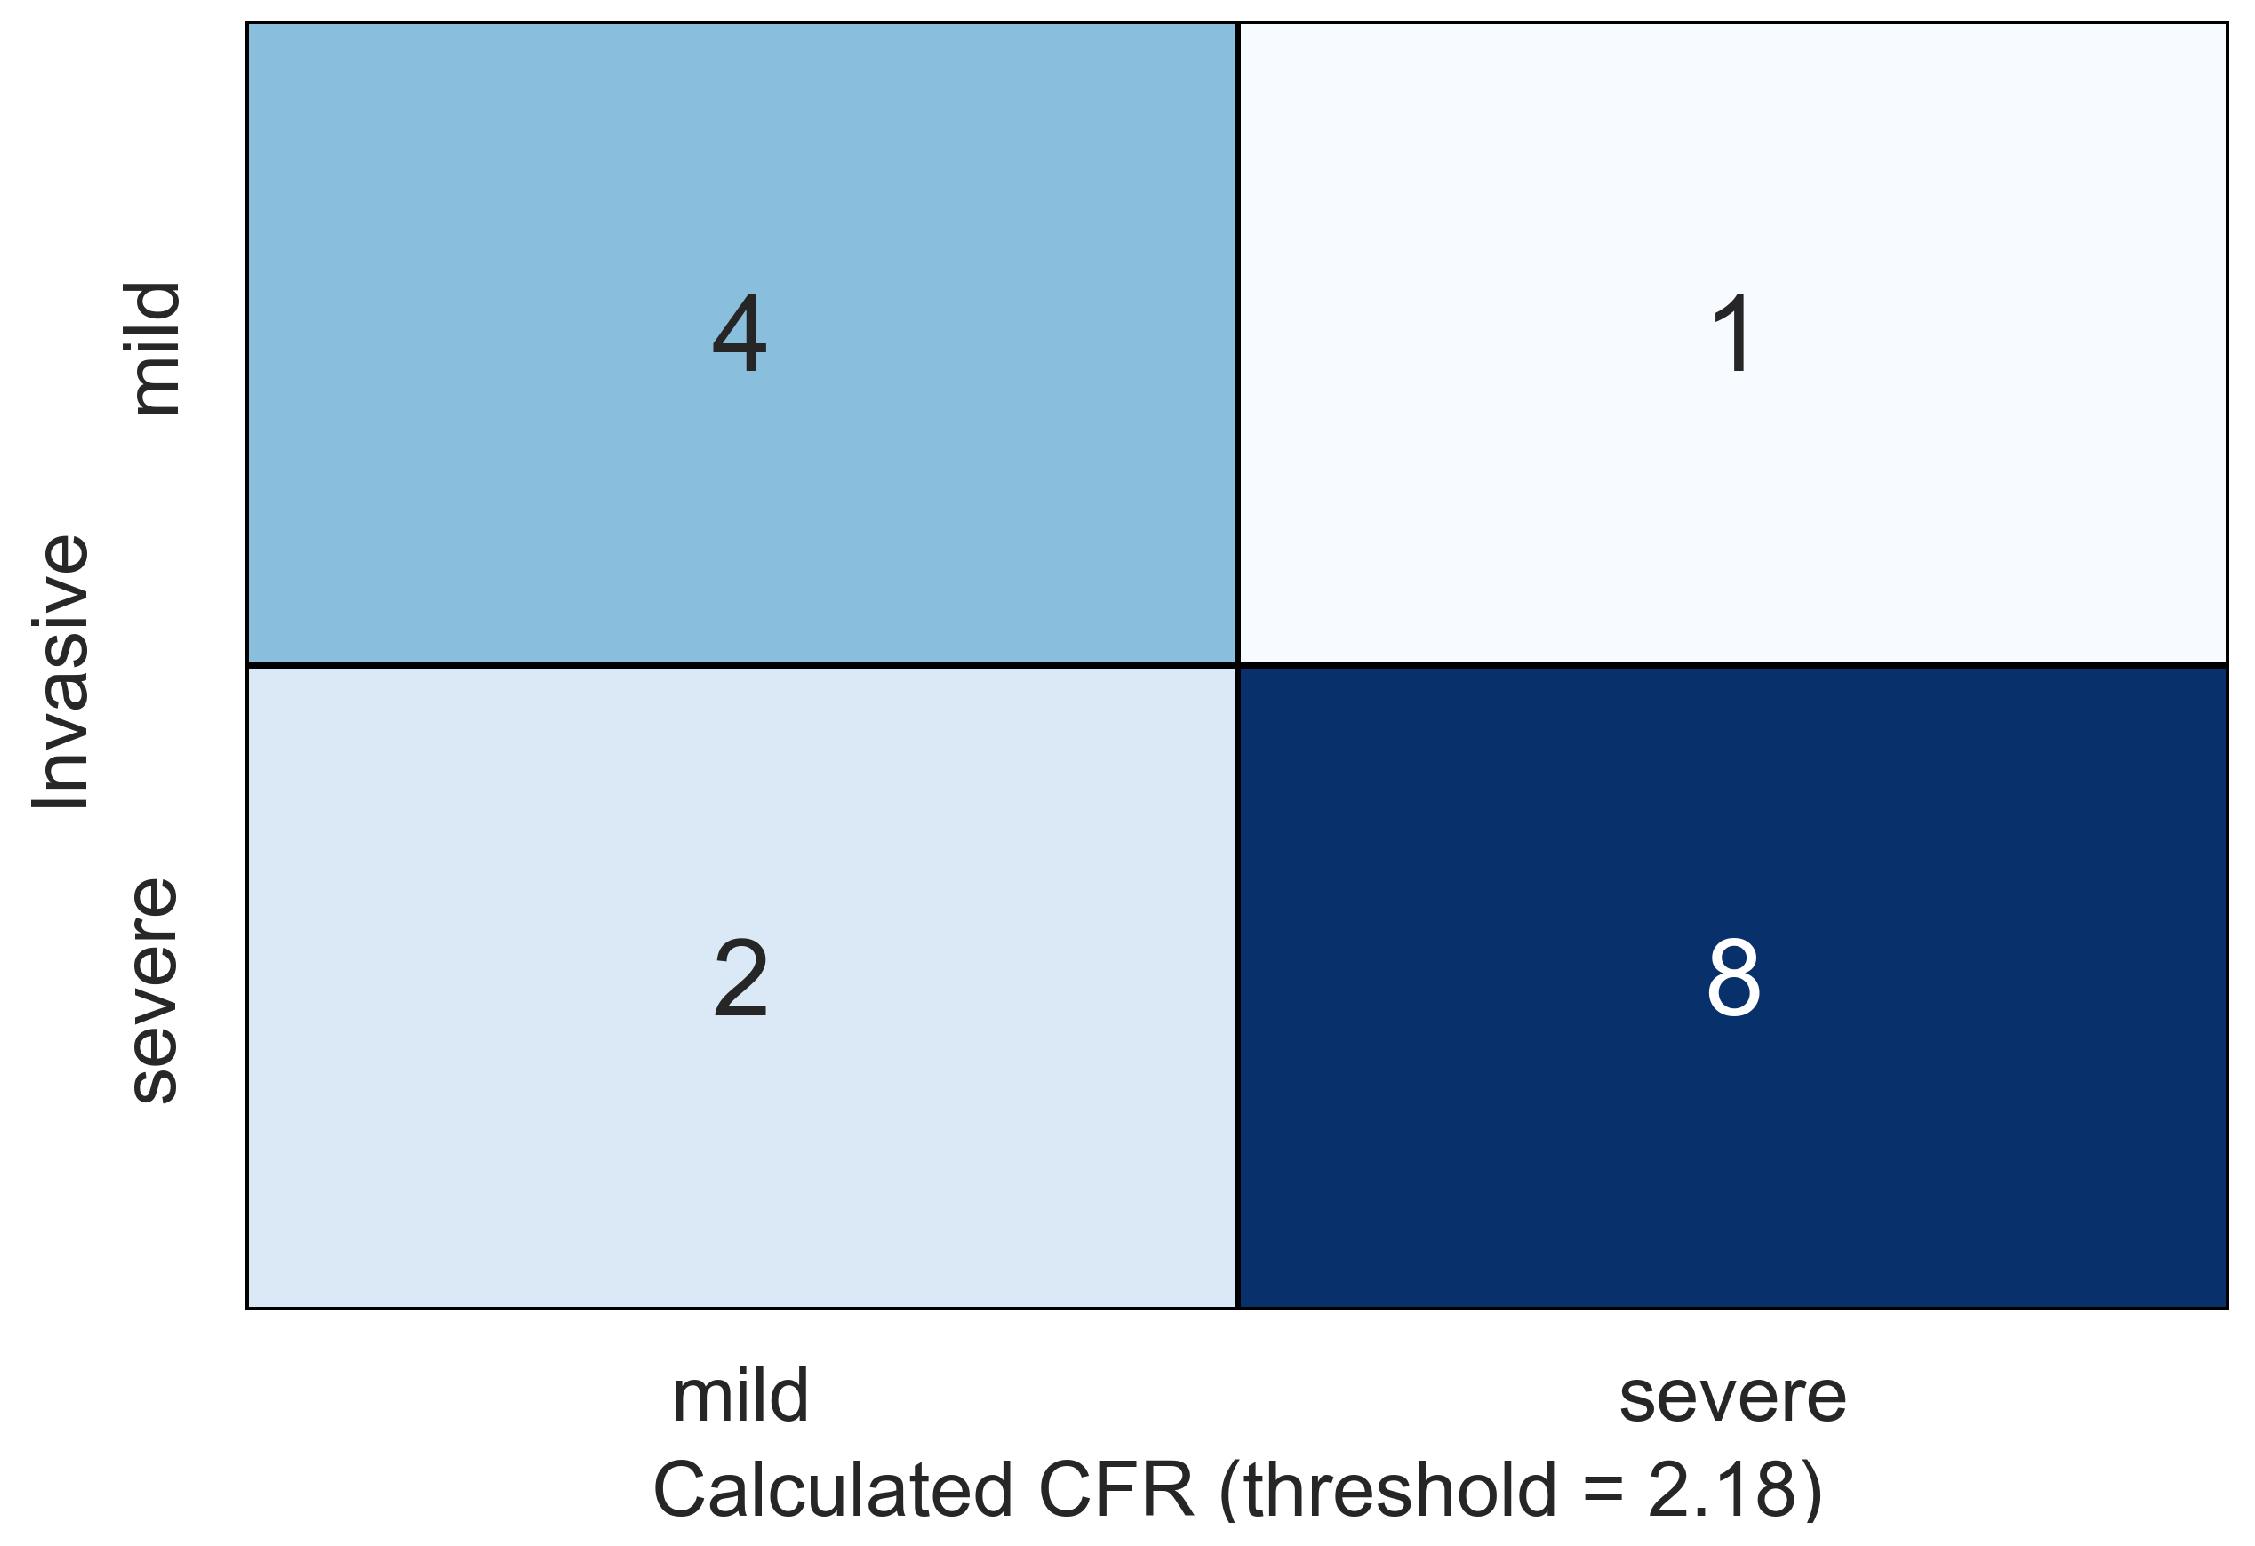

4. Results

5. Discussion